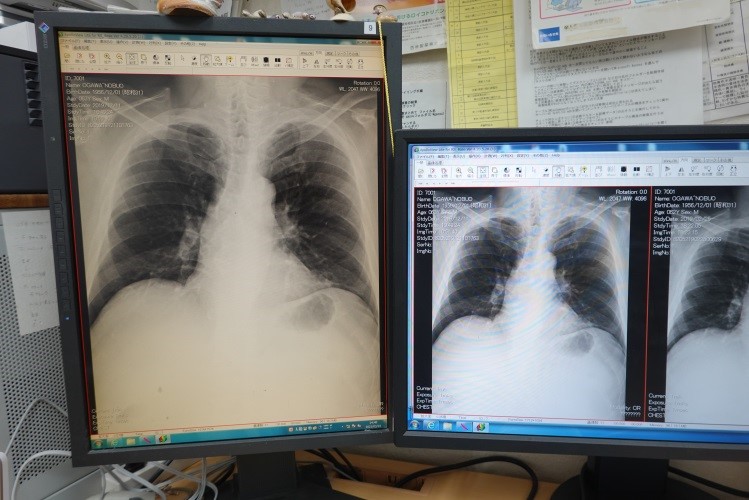

電子カルテを使った説明・診療

よくわかる説明を行うため、診療中に現在・過去の画像・検査データ・治療内容などをお見せできる電子カルテ(ダイナミクス)・自動ファイリングソフト(RS Base)をつかっています。 電子カルテには、患者さんの待ち時間を把握する、画像・検査データのプリントをお渡しする、診療終了時に会計ができているなどの利点があります。

診察机には、X線写真を診断するモニター、電子カルテ用のモニターがあり、パソコン内には病気の説明などの資料が準備されており、患者さんのよく理解できる説明に努めています。

X線検査:デジタル写真

X線写真を撮影すると、デジタル画像データが院内ランを経由して、診察室上の診断用高精細モニターにうつし出され、それを見て診断します。

現像したフィルムの診断と異なり、モニター上で画像の拡大・画質調整などの加工ができ、診断の助けとなります。